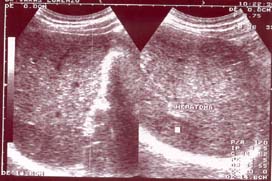

- Diagnóstico ecográfico precoz del cáncer hepático

El examen ecográfico seriado en enfermos cirróticos ha contribuido en los últimos años a un diagnóstico más precoz del cáncer hepático.En los pacientes con cirrosis o hepatopatía crónica por alcohol, virus B y C, hemocromatosis y porfiria fundamentalmente, se debe realizar una ecografía en ayunas cada 4-6 meses para la detección precoz del cáncer hepático, y de esta forma poder ofrecer al paciente la posibilidad de actuar terapeúticamente sobre él.

Si se detecta un nódulo mayor de 1 cm, se procederá a punción ecodirigida, y a practicar una TAC o RM.